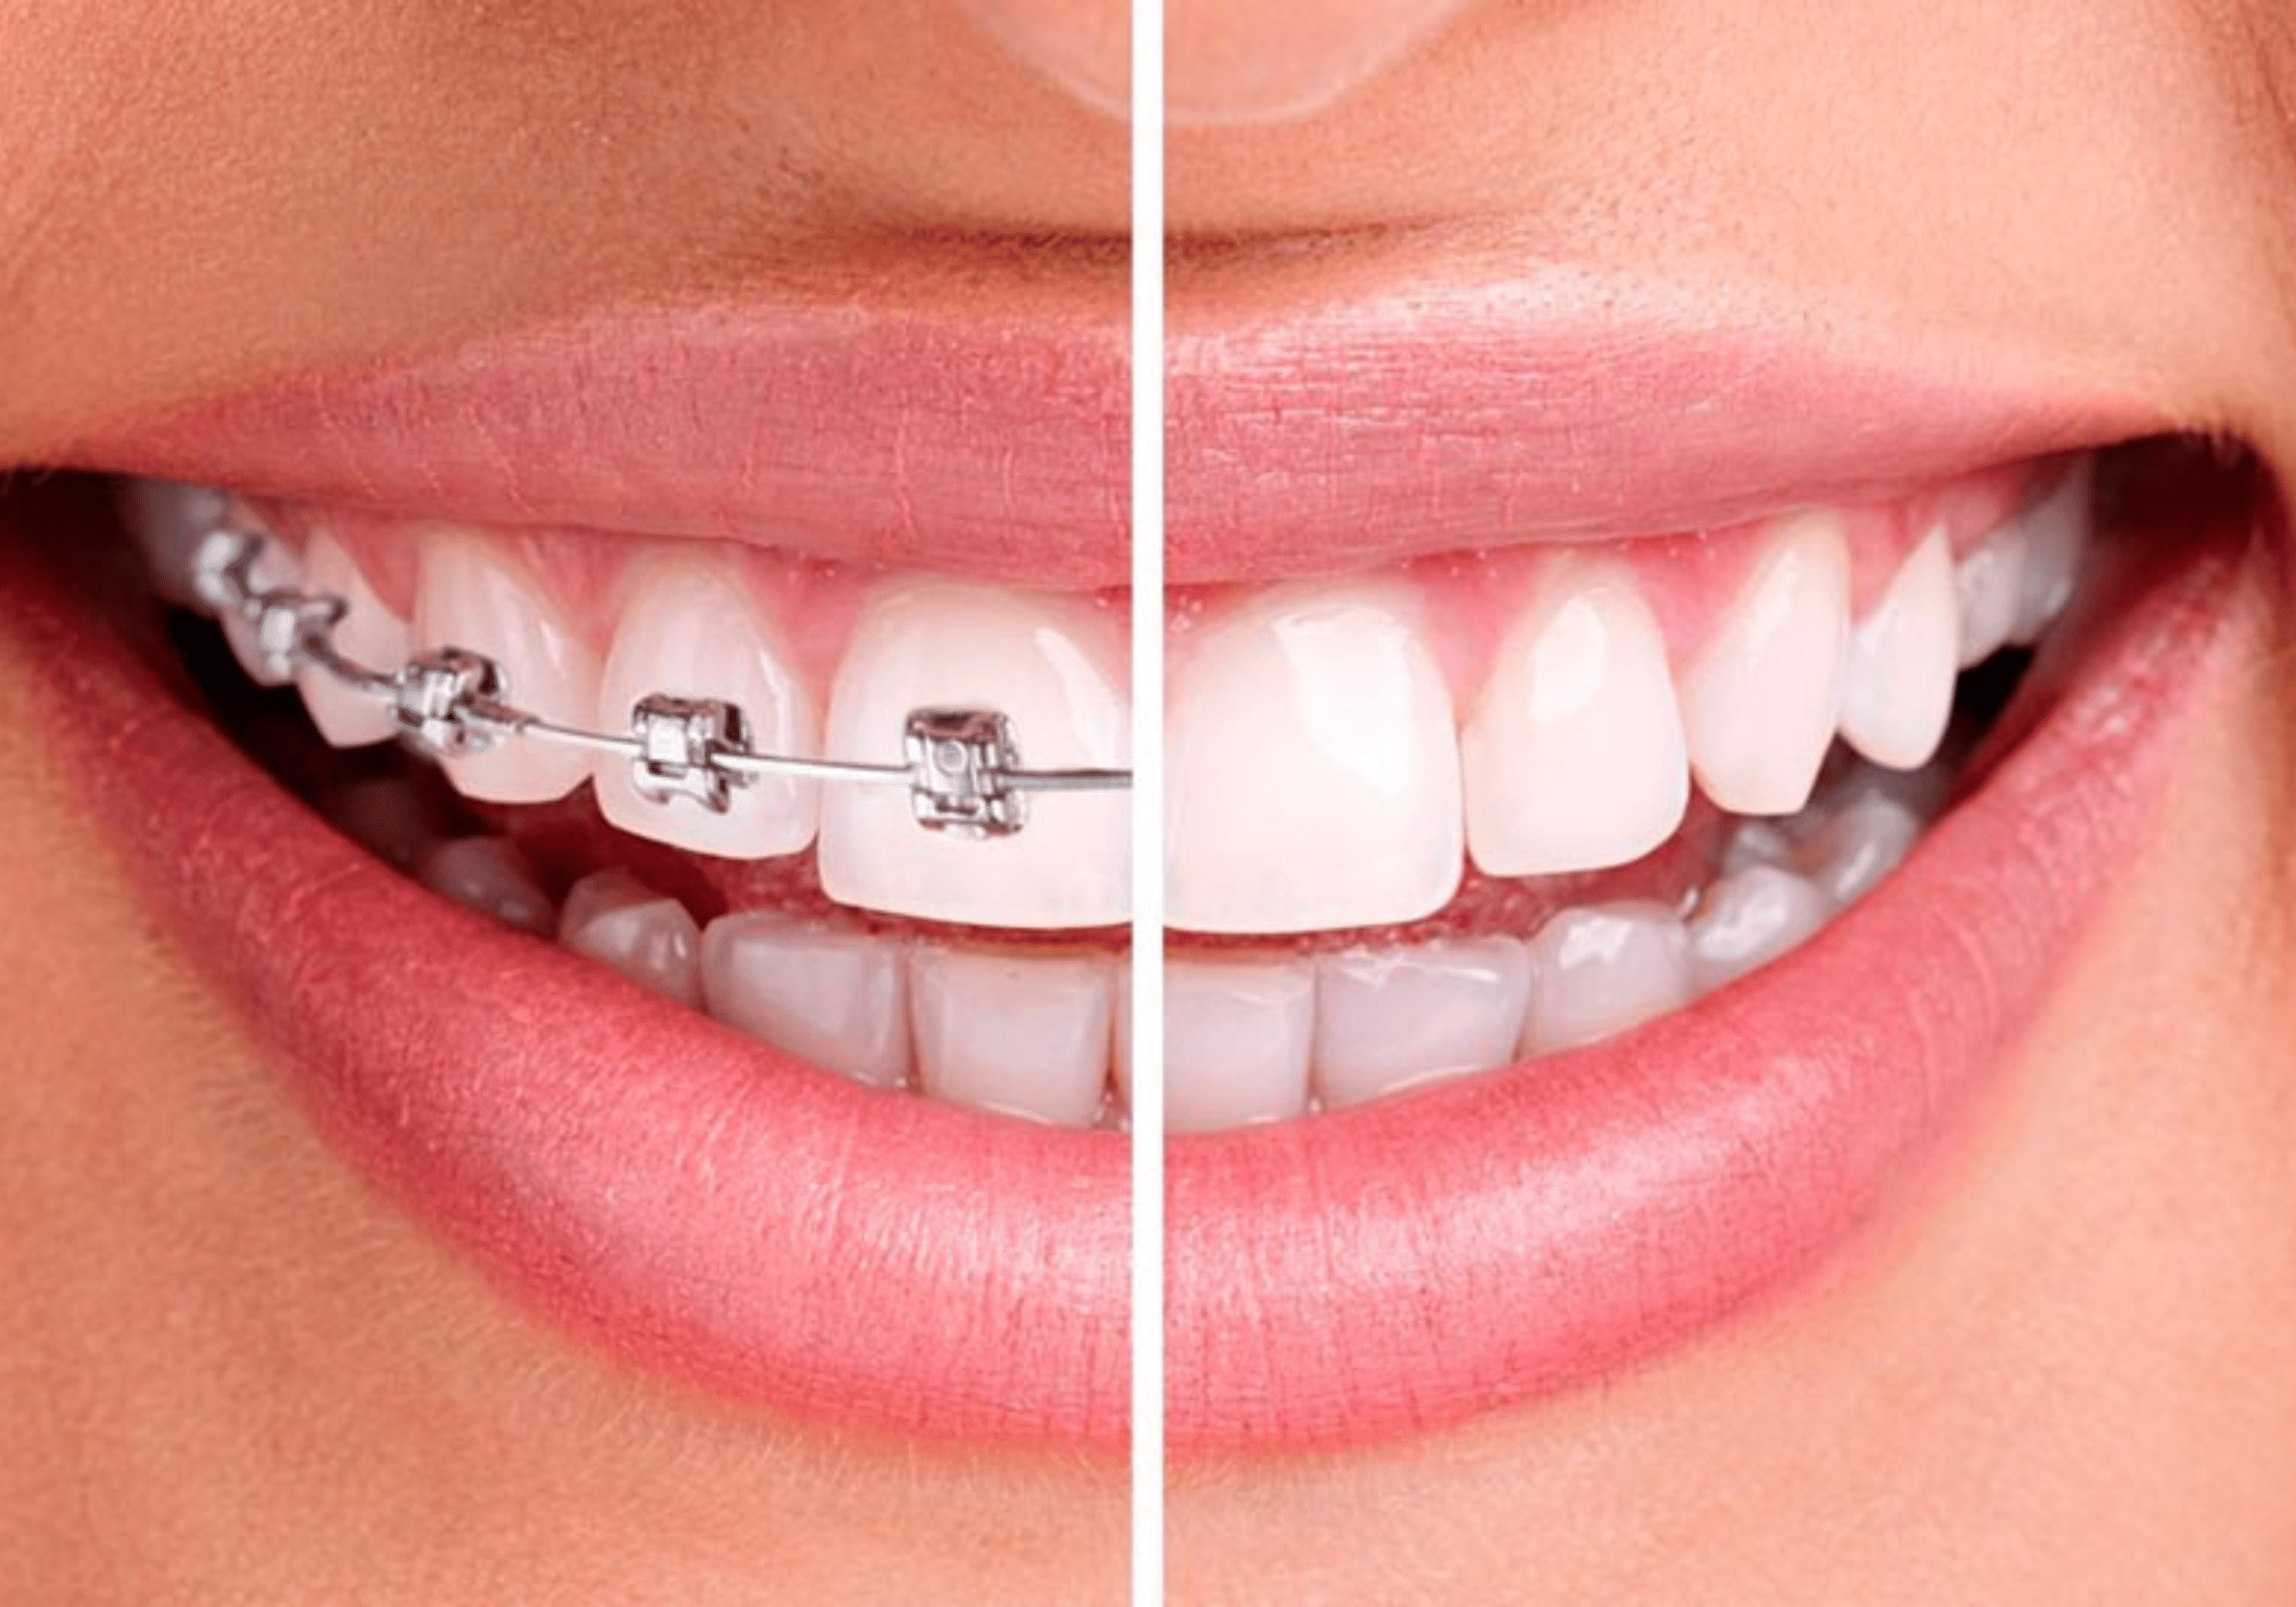

Bagues linguales outlet

Bagues linguales outlet, L orthodontie invisible pour les adolescents enfin une realite outlet

Orthodontiste Val de Marne 94 Interview d un patient avec beance outlet, Ma chirurgie Maxillo faciale Vlog 7 Appareil dentaire lingual temoignage outlet, Appareil Dentaire Adulte bagues lingual invisible Orthodontie Adulte outlet, Orthodontiste Paris Orthodontie linguale Paris outlet, L orthodontie invisible pour les adolescents enfin une realite outlet, Gouttieres invisibles ou bagues quelle solution choisir outlet, Bagues linguales hotsell ou invisalign outlet, L orthodontie invisible pour les adolescents enfin une realite outlet, orthodontie linguale Win specialite du cabinet du Dr Chassaing outlet, Lingual Braces The Dental Chambers Kensington outlet, Orthodontie adulte Dentiste Tremblay en France 93 outlet, Orthodontie Linguale a Paris Dr Issembert Orthodontiste outlet, Gouttieres invisibles ou bagues quelle solution choisir outlet, L orthodontie invisible pour les adolescents enfin une realite outlet, Appareil dentaire lingual pour les adulte Appareil Dentaire outlet, Orthodontie adulte outlet, Orthodontiste Val de Marne 94 Etapes de l Orthodontie Linguale outlet, Bagues linguales Orthodontie Lancy outlet, Bagues linguales ORTHODONTIE GARLABAN outlet, Orthodontie linguale finies les bagues apparentes outlet, Lingual Dr Soubrie Orthodontiste Voisins le Bretonneux Orthodontie 78 outlet, FAQ Quels sont les avantages et les inconvenients de l orthodontie linguale outlet, L orthodontie linguale SFODF outlet, Centre medico dentaire Blaise Pascal Dentiste a Trappes outlet, L essentiel sur les attaches linguales Centre dentaire des Tilleuls outlet, Orthodontie linguale Orthodontiste a Bordeaux Dr Francois Darque chirurgien dentiste outlet, Orthodontie Linguale toutes les infos a savoir Orthodontie Adulte outlet, Le traitement orthodontique lingual un appareil orthodontique totalement invisible outlet, Bagues et orthodontie le guide sur les differentes techniques outlet, Orthodontie Linguale Paris appareil dentaire lingual outlet, Orthodontie Linguale a Paris Dr Issembert Orthodontiste outlet, Les bagues et l orthodontie 3 grandes categories d appareils dentaires outlet, Lingual Orthodontics by Dr. Issembert Orthodontist outlet, Appareil dentaire invisible lingual Dr Ohana Chpindel outlet, Bagues linguales Orthodontie Lancy outlet, Product Info: Bagues linguales outlet.